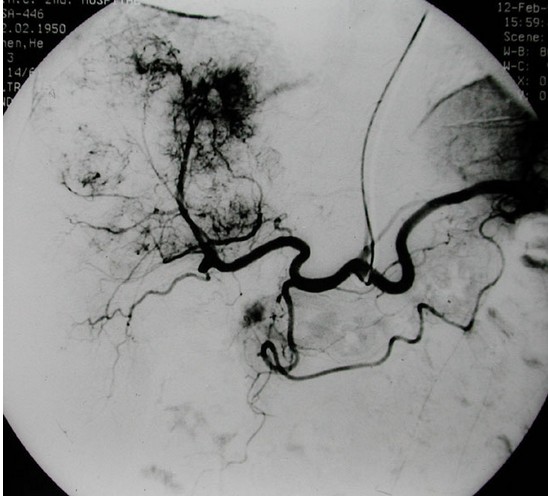

自1975年有学者报告经导管肝动脉栓塞术(transcatheter arterial embolization. TAE)治疗原发性肝癌以来,到目前已有很大改进。栓塞剂有:超液化碘油、明胶海绵、无水乙醇、碘油乳剂、各种中西药微球微囊等,可与抗癌药混合,利用不同方法经肝动脉灌注以阻断肿瘤的动脉血供、引起肿瘤坏死,同时使局部高浓度的化疗药物缓慢释放、较长时间作用于肿瘤细胞,杀灭肝癌细胞或抑制肝癌细胞生长,而化疗药物的全身毒性作用相对较小。

常用的栓塞途径有:经股动脉穿刺插管至肝固有动脉或肝动脉进行化疗栓塞术;经锁骨下动脉插管法等。